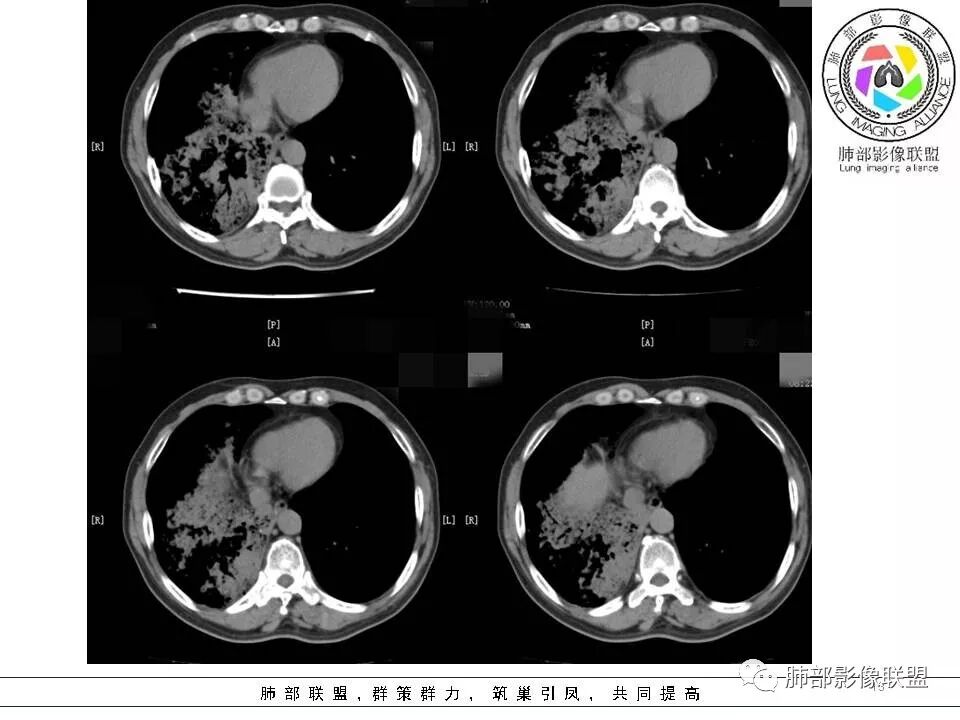

我们分析这2个病例的共同点:双肺都是以外周胸膜下分布为主,均表现为肺大片、斑片实变的肺炎性型改变,而且都有含气支气管的堵塞,这种残“支”败“叶”的异病同影的病例,那我们如何从影像上抽丝剥茧并结合临床分析病例呢?那我们现在按南边老师分析套路,从病变形态与分布、边缘的收缩性、病灶的走形方向、病灶的支气管变化、病灶内坏死及周围情况逐一分析;

病例一

病灶的形态与分布如何?

多发实变影,呈叶段分布,形态及密度都比较单一,比较柔和

病灶的走形如何?                                                                                                以外围胸膜下分布为主,长轴与胸膜平行

病灶的边缘如何:

大部分边缘膨隆,局部边缘稍收缩

病灶内的支气管如何:                                                                            支气管走形通畅自然,部分于近端堵塞,管壁光整

病灶内的坏死如何?:                                                                                             病灶内有坏死空洞,大部分空洞内壁光整,部分空洞内少许分隔影,呈“鬼脸”样空洞

周围情况如何?:                                                                                                   周围肺野有模糊晕,未见明显树芽征,与胸膜有糊墙改变

患者临床轻影像重,CRP增高,社区获得性肺炎常规不考虑,年轻人,不是许多机会性感染的易感人群,特殊性感染性病变有结核和隐球,但是结核形态多发,好发于上叶及下叶背段,密度不均一,通常有树芽,而且结核空洞呈虫蚀样且内壁光整,不作为首先考虑病灶形态单一,有晕征,有空洞及空洞内分隔,病灶分布与胸膜平行,隐球比较符合,但是结核影像多样化,年轻人,也需要临床进一步检查除外结核。    病例为什么不首先考虑OP或淋巴瘤,病灶内支气管情况有助于判别,OP收缩性往往很强,所以病灶内支气管应该稍扩张而且没有堵塞,淋巴瘤起源于支气管粘膜下和肺间质,往往沿血管支气管束方向分布,与胸膜垂直为主,病灶内支气管壁增厚并直达远段,易合并支气管扩张;年轻人肺炎型肺癌少见,而且影像表现也不支持,如果患者治疗效果不好,需要临床进一步检查排查肺癌。